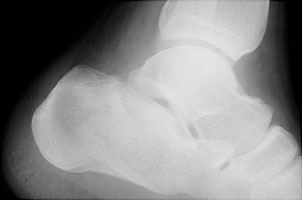

B | Lateral radiograph of the ankle. This shows flattening of Boehler's angle and sclerosis through the calcaneus. |